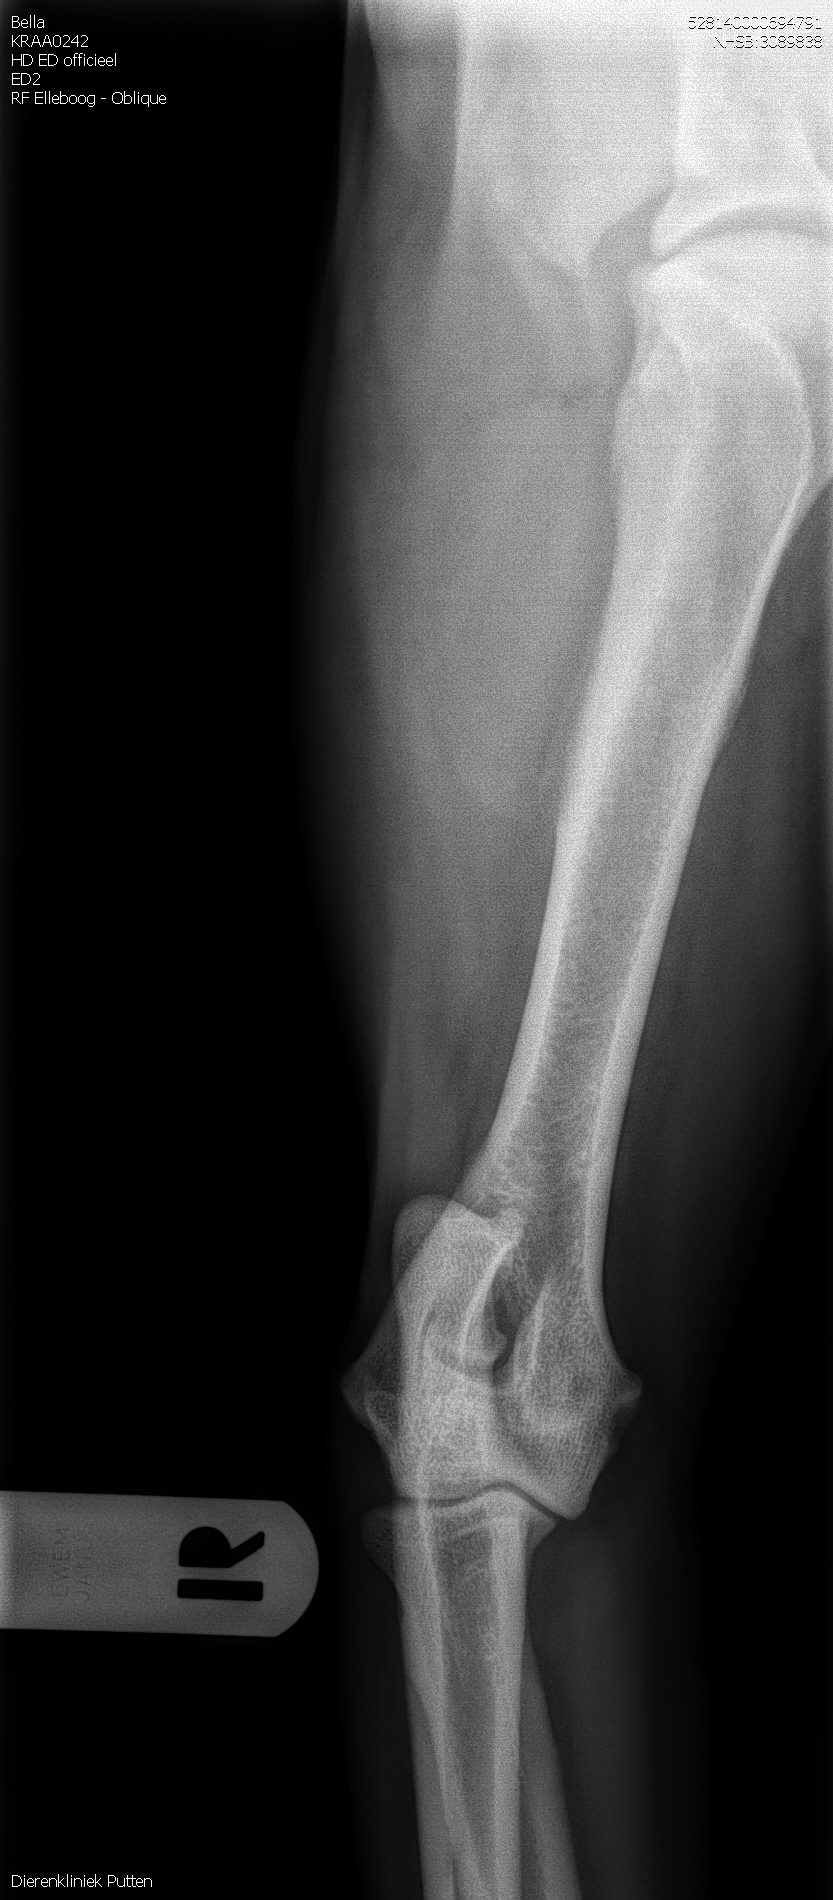

HD-A (Norbergwaarde 37.5, Botafw. 0), ED-0, Rug 100%

Röntgen foto’s Bella